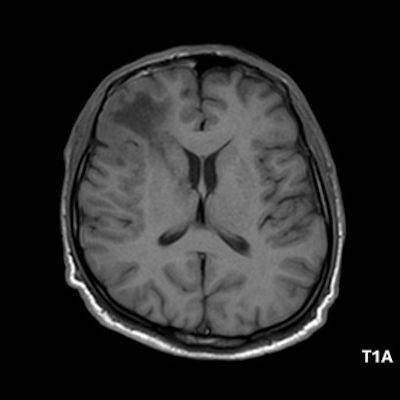

1. A) Aksiyel T2A görüntülerde bilateral sağda belirgin frontoparietal subkortikal ve derin periventriküler beyaz cevherde subkortikal U fiberleri boyunca yerleşimli sinyal artımları (oklar) izlendi.  Tarifli alanlar aksiyel T1A serilerde hipointens görünümde (oklar) izlendi.

1. PML’de MRG bulguları genellikle multifokal, asimetrik periventriküler ve subkortikal beyaz cevher tutulumu şeklindedir. Subkortikal U-fiberleri sıklıkla tutulur, özellikle parietooksipital bölgelerde belirgin lezyon eğilimi vardır.

2. T1 ağırlıklı görüntülerde tutulan bölgeler hipointens, T2A’da ise hiperintens izlenir. Ana lezyon çevresinde çok sayıda noktasal (milkyway) sinyal artımları görülebilir. Ayrıca spleniumu çaprazlayan parietooksipital sinyal değişiklikleri (barbell bulgusu) ve dentat nukleusu koruyarak serebellar beyaz cevher tutulumu (shrimp bulgusu) da tanımlanmıştır.

4. Bizim hastamızda bilinen HIV enfeksiyonu mevcuttu ve yapılan kraniyal MR görüntülemede multifokal, asimetrik, periventriküler ve subkortikal beyaz cevherde yerleşimli, kitle etkisi göstermeyen ve kontrastlanmayan lezyonlar izlendi. Lezyonların subkortikal U-fiberleri tutması ve özellikle parieto-oksipital bölgelerde belirgin olması nedeniyle ön planda PML düşünüldü. Histopatolojik tetkik ile PML tanısı doğrulandı.